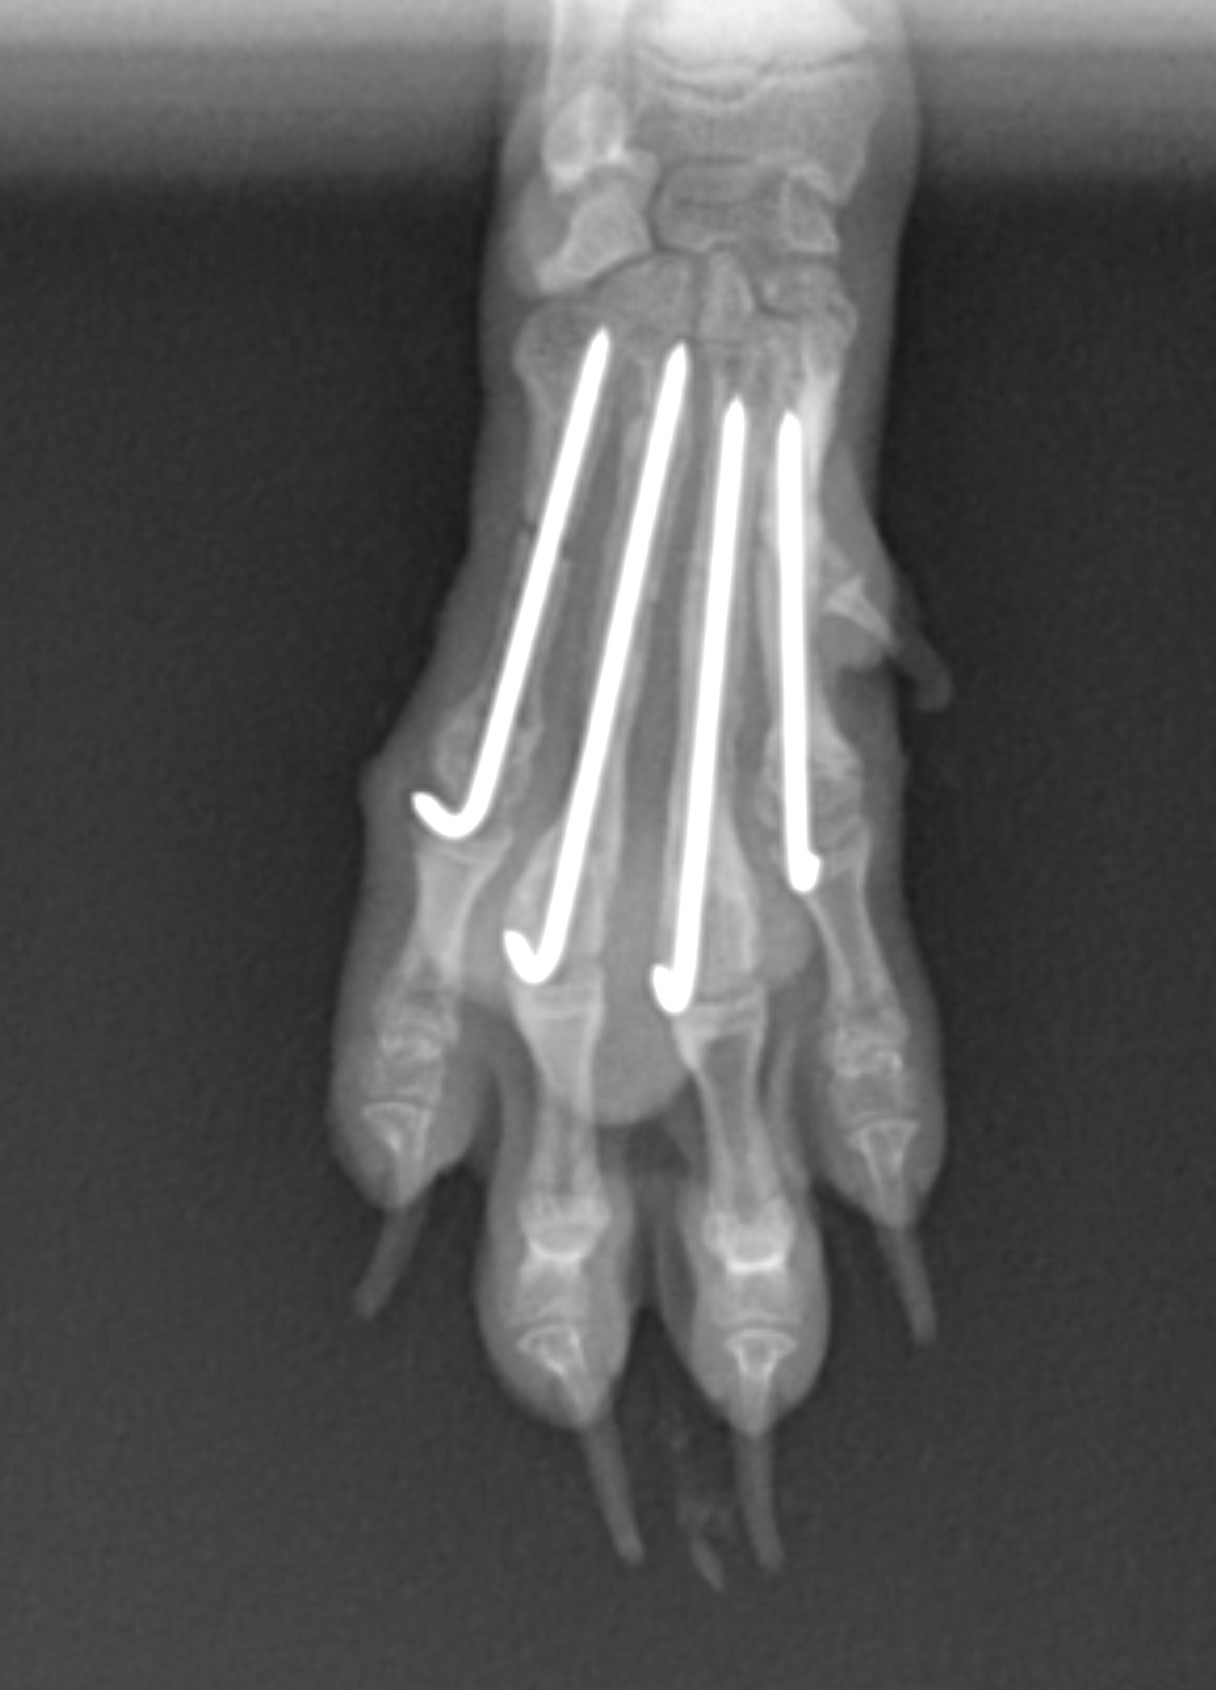

ピンを挿入したままだと骨折部位は癒合しても細くなり、再骨折を起こしかねません。そのため、

ピンを段階的に抜去し、抜去した部位の骨が再骨折しないように外固定も併用し慎重に経過をみてい

きます。 最終的にはすべて抜去し完治にいたります。